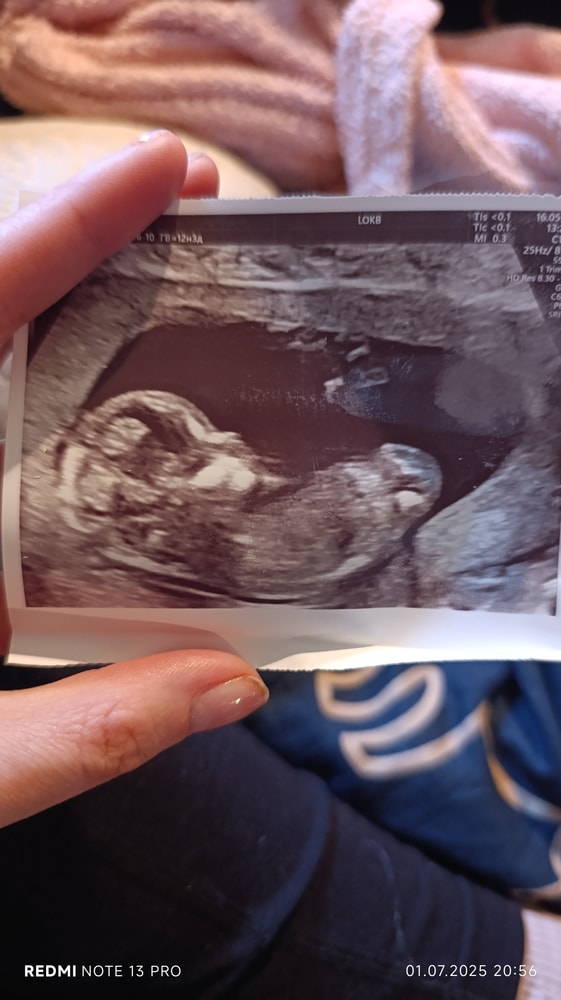

Решила посмотреть фото УЗИ первого скрининга, смотрю многие по нему определили пол🫣

Узи сделано в 12 недель 4 дня

Но по УЗИ срок 13 недель и 1 день

Я даже бугорка не вижу😂